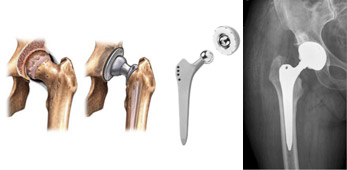

La sostituzione protesica dell’articolazione dell’anca comprende il versante acetabolare (del bacino o cotile) e quello femorale: si parla di artroprotesi. Nei casi di frattura del collo del femore, quando la cartilagine del cotile è ancora buona, è possibile protesizzare solo la componente femorale: si parla di endoprotesi.

Esistono svariati tipi di protesi, differenti per design (steli a conservazione del collo, steli retti e anatomici, cotili emisferici, tronco-conici, modulari) e concetto di fissazione (cementato, non cementato, a press-fit o avvitato).

La scelta del tipo di impianto dipende dalla patologia specifica, da condizioni locali e/o generali del paziente e dall’esperienza e filosofia del chirurgo.

In generale, le protesi non cementate e a risparmio osseo, si utilizzano maggiormente nei pazienti giovani e attivi; le protesi cementate si utilizzano, invece, quando la qualità dell’osso non è buona (es. pazienti in età molto avanzata, osteoporosi, ecc.).

Le nuove tecniche di cementazione e la qualità dei cementi moderni garantiscono ottimi standard qualitativi sia in termini di resistenza, che di ancoraggio della protesi all’osso e di sopravvivenza dell’impianto a lungo termine.

La protesi d’anca è costituita da uno stelo che viene inserito nel canale femorale, dal cotile che viene impiantato nella corrispondente porzione del bacino e dallo snodo, composto da una testina, da un collo e dall’inserto cotiloideo.

I materiali di cui sono composte le protesi sono generalmente leghe metalliche prevalentemente in titanio (che risulta il materiale con le caratteristiche meccaniche - il cosiddetto modulo di elasticità – più simili all’osso). Le superfici di scorrimento, essendo sottoposte a frizione, devono ridurre il più possibile l’usura e sono costituite prevalentemente da leghe metalliche (cromo-cobalto-molibdeno), materiali ceramici e plastici (polietilene).